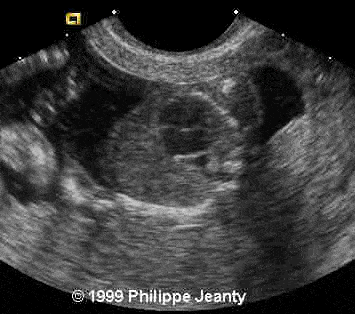

17-year-old primigravida.

This examination is obtained at 18 weeks amenorrhea.

• small stomach

Very few, however, made the most crucial observation: the great disproportion between the head and abdomen. That disproportion is very typical of triploidy (see the lecture on aneuploidy for another example) and I know of no other conditions where such a big difference exist without a concomitant intracranial anomaly such as hydrocephaly, or teratomas… Of course, one of you will come up with a great differential diagnosis and then we will learn even more !

Too small stomach.

An enlarged eye, and mainly the disproportion between the head-abdomen size.